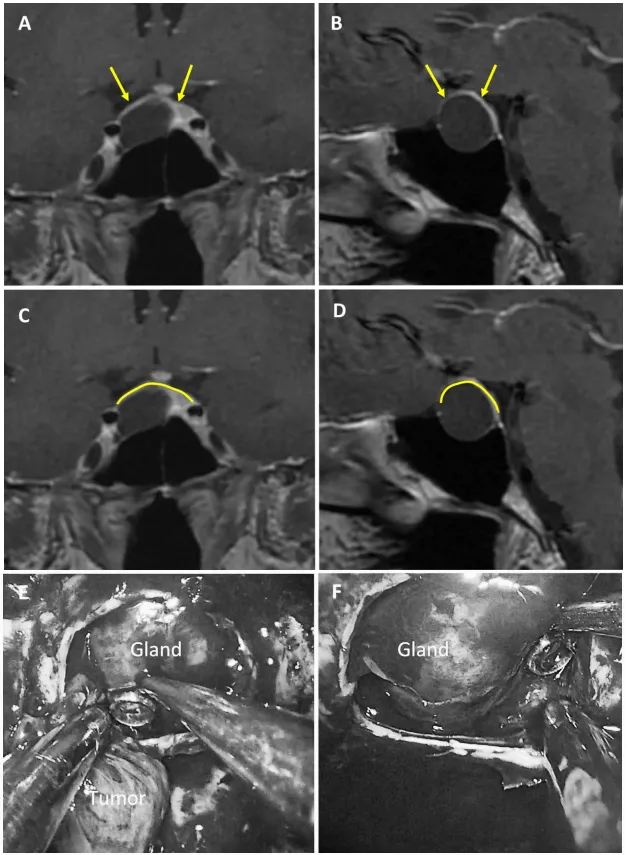

2. 混合型鞍隔屏障案例

图5展示56岁女性ACTH腺瘤患者。a和b为术前MRI图像,黄色箭头指示厚度大于1毫米的强化屏障区,红色箭头指示厚度小于1毫米的薄弱屏障区;c和d为术前MRI,黄色标记线标示强韧屏障区域,红色标记线标示薄弱屏障区域;e为术中图像,显示由垂体腺与蛛网膜共同构成的混合屏障结构。